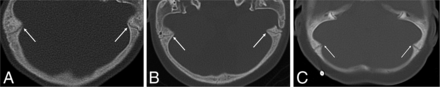

Two hundred eighty-six brain MR imaging studies in 61 patients from 1996 to 2015 were reviewed. Fifty-seven of the 61 (93.4%) patients reviewed were found to have varying degrees of posterior fossa horns at some time point during this period. Ages ranged from 1 month to 20 years, with a mean age of 4.7 years and median age of 3.4 years. Among patients who had posterior fossa horns, the average age at their first scan was 1.6 years, and among patients who did not have posterior fossa horns during this period, the average age at their first scan was 11.2 years. There was no statistical difference between the left and right posterior fossa horns (P > .01). Three patients had CT scans showing coexisting open occipitomastoid sutures and posterior fossa horns at an early age (Fig 2). The average left and right posterior fossa horns were largest before 1 year of age, 5.8 mm and 6.7 mm, respectively, and the sizes progressively decreased as the patients aged (Table and Fig 3). There is a significant negative correlation (R2 = 0.23, P < .01, and R2 = 0.32, P < .01) between the size of both left and right posterior fossa horns and age. The longitudinal regression of the posterior fossa horns is illustrated in 29 patients who each had ≥5 scans and received a hematopoietic stem cell transplant, which shows that the decrease in size of the posterior fossa horns started before transplantation (Fig 4).

CT images show bilateral internal hypertrophy yet open occipital mastoid sutures (white arrows) in 3 different patients with MPS IH. A, This is the first patient with CT at the head bone window obtained at 1 year of age. B, This is the second patient with CT at the head bone window obtained at 1.6 years of age. C, This is the third patient with CT at the head bone window obtained at 1 year of age.

Skull sutures serve as sites of intramembranous bone growth, and their timed expansion allows brain growth.12 The fusion patterns vary depending on the suture, and particularly, the occipitomastoid suture only partially closes in <30% of healthy individuals and can stay open even in the ninth decade.13,14 Oussoren et al11 examined the incidence of early closure of major sutures in patients with mucopolysaccharidosis and showed that as many as 11 of 14 patients with MPS IH (71%) had early major suture closure resulting in craniosynostosis. However, to our knowledge, there is no study examining the minor sutures in patients with MPS IH. While CT scans were not commonly performed in our cohort, we found 3 separate cases with large posterior fossa horns and open occipitomastoid sutures, suggesting that the prominence of the posterior horn was not due to early suture closure as postulated in the early study involving major sutures but rather likely due to the effects of MPS IH (Fig 2).